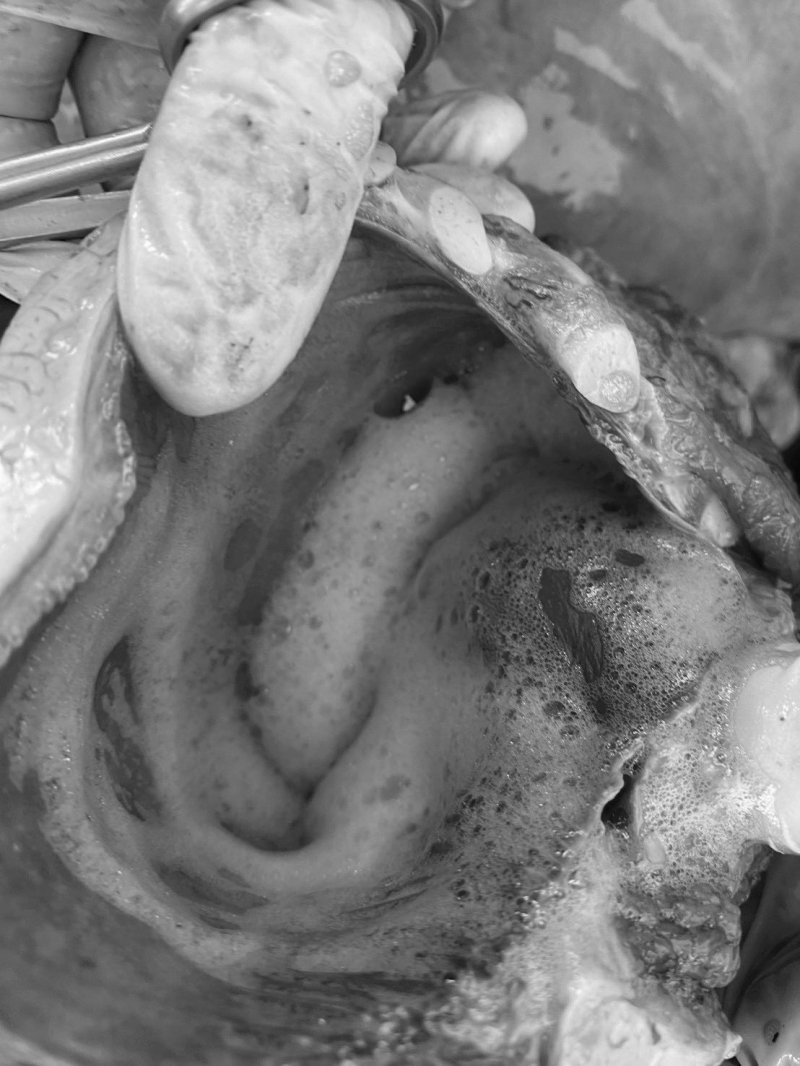

เมื่อเปิดผ่าชันสูตรดูอวัยวะภายในพบว่าหัวใจมีเลือดคั่งและบวมน้ำเล็กน้อย ส่วนของทางเดินหายใจพบฟองอากาศและของเหลวคั่งภายในหลอดลมและเนื้อเยื่อปอด ปอดบวมน้ำ บริเวณเนื้อเยื่อปอดด้านนอกพบลักษณะปื้นสีดำรูปร่างไม่แน่นอน ขนาดประมาณ 1-2 ซม. ส่วนของทางเดินอาหารไม่พบอาหารและสิ่งแปลกปลอมภายในทางเดินอาหาร

สาเหตุการตายเกิดจากการจมน้ำ โดยคาดว่าสาเหตุโน้มนำเกิดจากการป่วยและพลัดหลงจากแม่ ทั้งนี้ เจ้าหน้าที่ได้ทำการเก็บตัวอย่างชิ้นเนื้อเพื่อนำไปวิเคราะห์ทางห้องปฏิบัติการ ตัวอย่างโครงกระดูกส่วนขากรรไกรล่าง ครีบอก กระดูกเชิงกรานและทำการจัดการซากโดยได้รับความอนุเคราะห์จากองค์การบริหารส่วนตำบลปูยู จังหวัดสตูลเพื่อใช้รถแมคโครในการขุดฝังกลบซากในพื้นที่